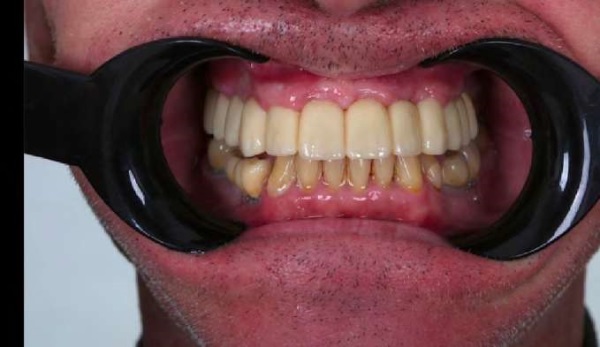

Исходами хирургического и ортопедического вмешательств являлись полноценная реабилитация верхней челюсти, полное заживление слизистой оболочки, восстановление функций речи и жевания (рис. 16, 17). Каких-либо конструкционных или функциональных нарушений выявлено не было.

Рис. 16. Пациент А. сразу после постоянного протезирования

Примечание: фотография выполнена авторами.

Fig. 16. Exterior view of the oral cavity in patient A. immediately after the placement of a permanent prosthesis

Note: The photograph was taken by the authors.

Рис 17. Пациент А. сразу после постоянного протезирования

Fig. 17. Patient A. immediately after the placement of a permanent prosthesis